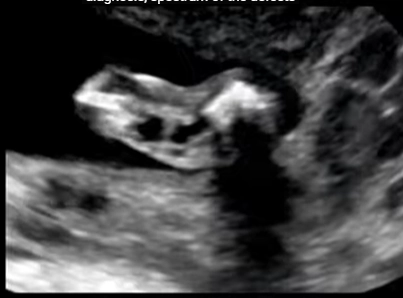

• XII. Hệ cơ xương khớp thai nhi

• Giải phẫu siêu âm cơ xương khớp quý I

• Loạn sản xương quý I (Skeletal dysplasias)

• Cơ xương khớp thai

• Tổng quan CXK

• Tổng quan cơ xương khớp thai nhi (Approach to fetal skeletal)

• Chẩn đoán phân biệt

• Ngắn nhẹ xương đùi / xương cánh tay thai (Mildly Short Femur / Humerus)

• Xương cong ở thai nhi (Curved / Angulated Bones)

• Bất thường cốt hóa thai (Abnormal Ossification)